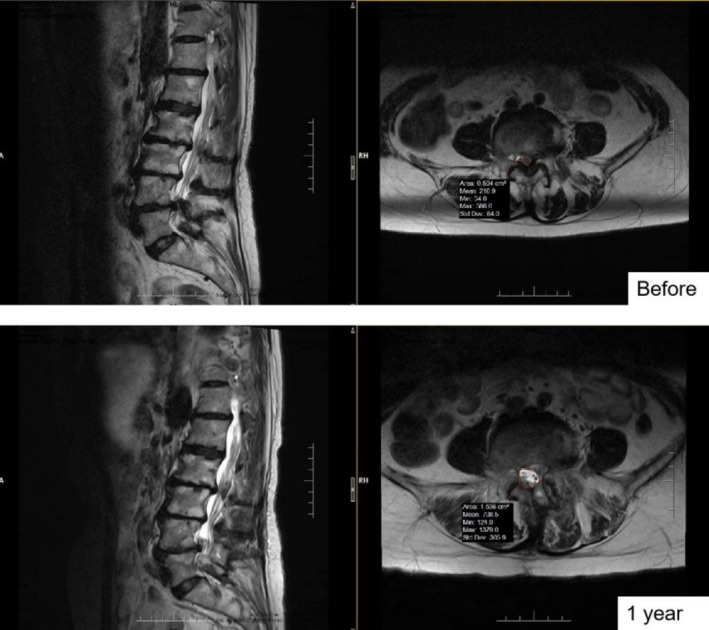

Methods: We retrospectively identified 41 and 47 patients who underwent BE-ULBD and ULBD, respectively, who were diagnosed with multi-level lumbar stenosis and underwent double-segmental surgery in elderly patients. The clinical outcomes were evaluated using visual analogue scale (VAS) score for both back and leg pain, Oswestry Disability Index (ODI) score, and Zurich Claudication Questionnaire score during the two-year follow-up. The radiological changes of cross-sectional dural area (DCSA), facet joint preservation rate (PFJR) and cross-sectional fat infiltration ratio (FI) on the surgical side were evaluated by MRI before and after operation. At 2 years after operation, progressive spondylolisthesis and instability were evaluated in the X-ray of the lumbar spine.

Results: After 24 months of follow-up, the VAS scores for both back and leg pain, ODI, and Zurich Claudication Questionnaire in both groups were recovered compared to pre-operation. The postoperative VAS score for lower back pain in the BE-ULBD group was lower than in the ULBD group (1.00 ± 0.95 vs. 1.91 ± 1.07, p < 0.001), and the postoperative VAS score for lower limbs was similar (0.49 ± 0.51 vs. 0.46 ± 0.72, p < 0.001). The postoperative ODI score was lower than that of the ULBD group (9.05 ± 5.01 vs. 12.09 ± 6.18, p < 0.001), and the postoperative ZCQ score of the BE-ULBD group was lower than that of the ULBD group (10.59 ± 2.18 vs. 8.85 ± 1.59, p < 0.001; 7.00 ± 1.12 vs. 7.87 ± 1.63, p = 0.012; 8.95 ± 2.11 vs. 10.74 ± 2.47, p < 0.001). In terms of radiological evaluation, the DCSA of patients in both groups was effectively improved after surgery. Compared with the ULBD group, the BE-ULBD group had a tiny improvement in DCSA (195.04 ± 34.54 vs. 180.93 ± 31.07, p = 0.048) and a better FI (43.48 ± 10.24 vs. 53.93 ± 7.62, p < 0.001). The PFJR was higher (85.90 ± 4.03 vs. 81.26 ± 4.56, p < 0.001) in the BE-ULBD group. Two years after surgery, fewer patients in the BE-ULBD group had spondylolisthesis than in the ULBD group (1/41 vs. 7/46, p = 0.043). The results of complications were similar between the two groups.